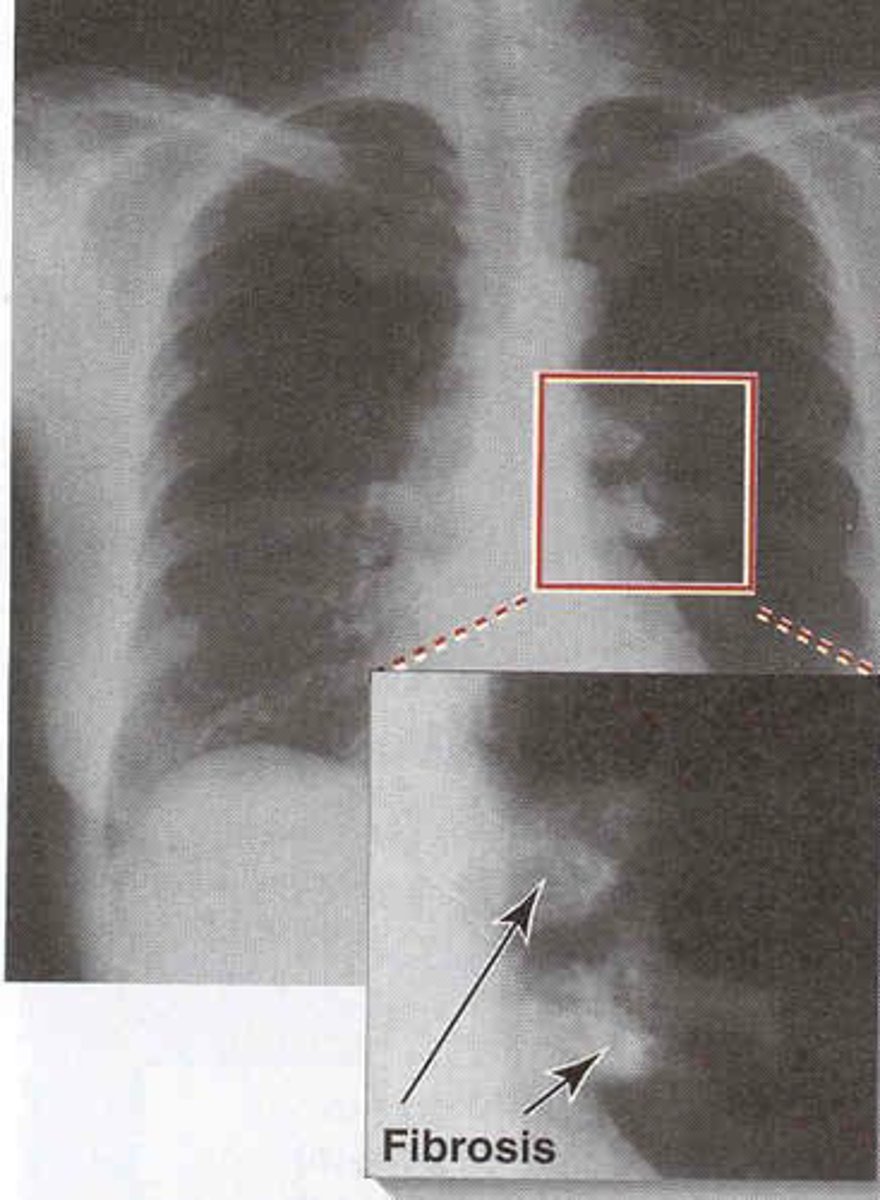

What causes 'Miliary TB'?

Systemic spread of Mycobacterium tuberculosis via blood, appearing as tiny spots on X-ray.